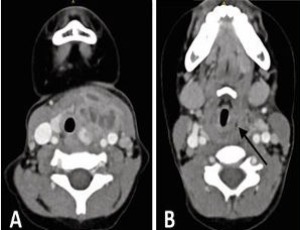

Flexible Endoscopic Diagnosis of Fourth Branchial Cleft Sinus in Children A Case Series